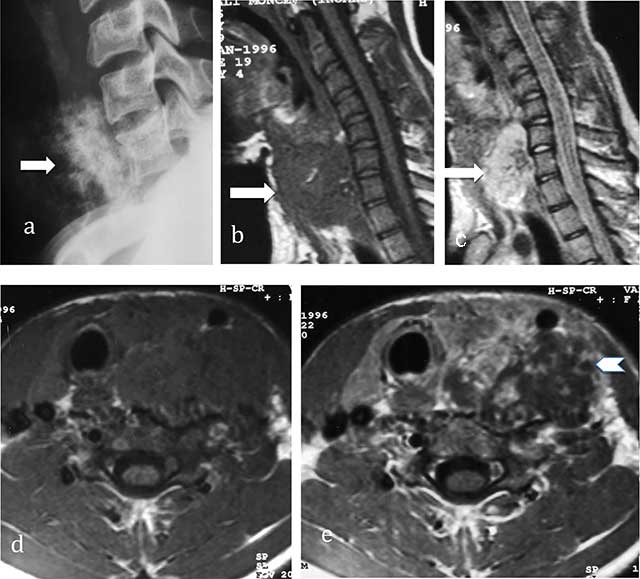

Figure 3

Chondrosarcoma of C7. (a) Lateral radiograph of cervical spine shows a large iuxta-osseous calcified mass arising from the vertebral body of C7 (arrow). (b, c, d, e) MR: Sagittal T1-WI, Sagittal T2-WI, Transversal T1-WI, Transversal T1-WI after gadolinium contrast injection show lobulated mass of intermediate signal intensity on T1-WI and high signal intensity on T2-WI (arrows) with ring-and-arc enhancement (arrowhead).